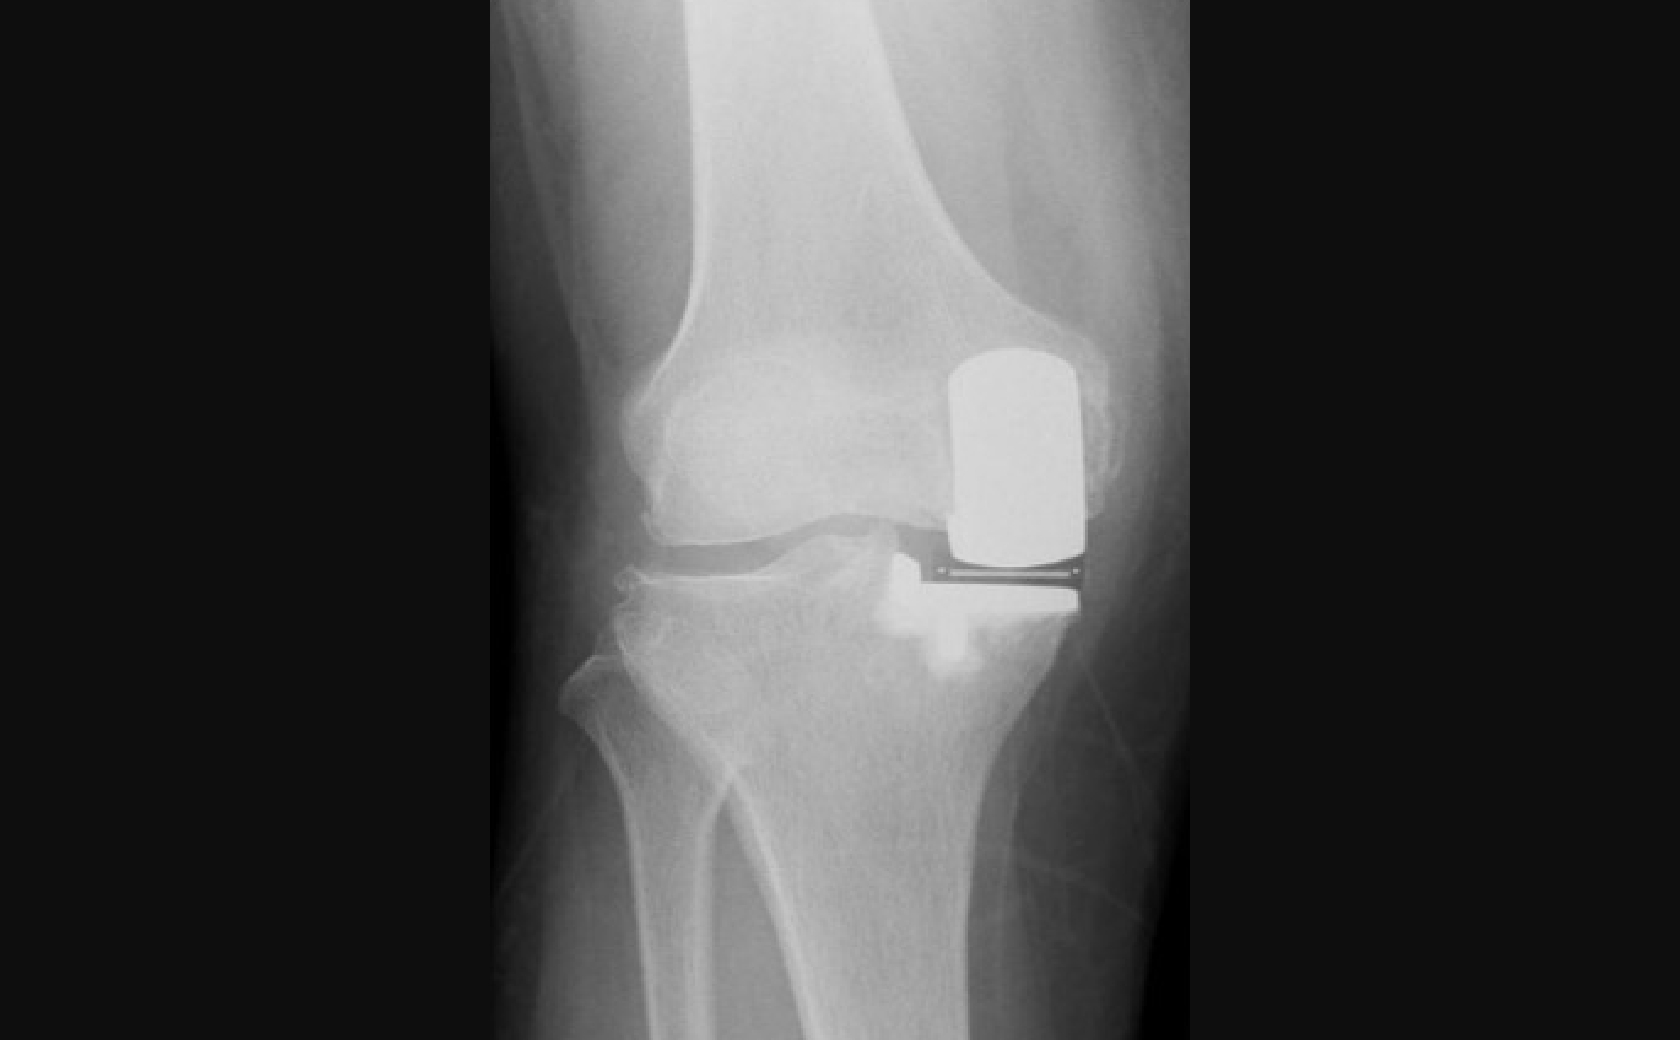

手術前後レントゲン画像

全人工膝関節置換術

術後